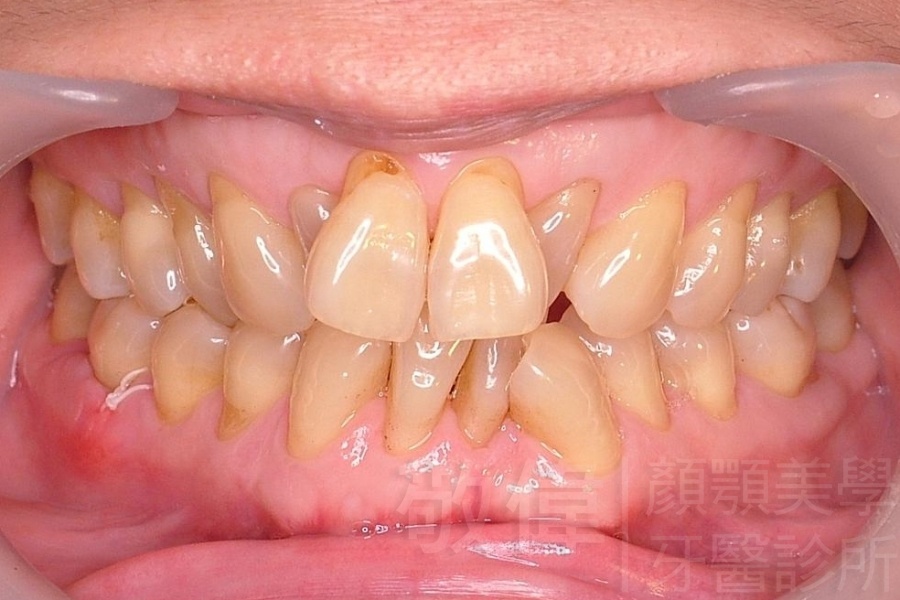

齒顏矯正/上顎暴牙且牙齒極度混亂

矯正前-右   矯正前-正   矯正前-左

<個案說明>

上顎暴牙且牙齒極度混亂,經由矯正之後,臉型大幅度改善,牙齒的排列更加的整齊健康。相較於之前眼神充滿精神,自信心展現無遺。